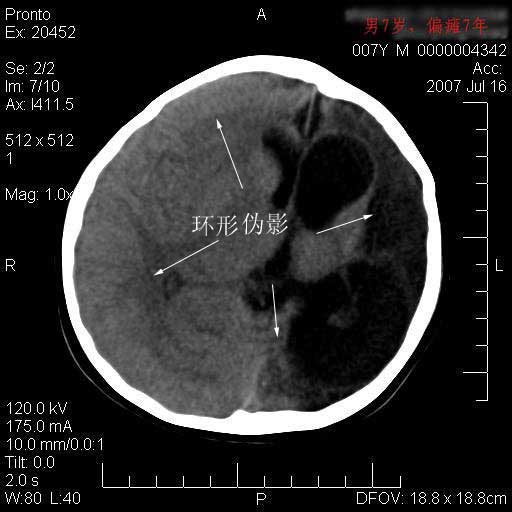

(另ct机器有伪影,需校正。)